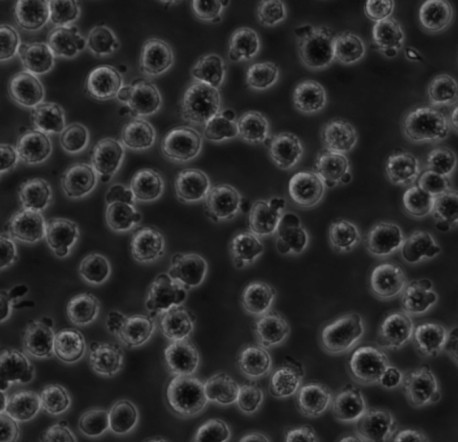

OCI-AML3

OCI/AML-3; OCI-AML3; OCI/AML3; OCI AML3; OCIAML3; Ontario Cancer Institute-Acute Myeloid Leukemia-3

悬浮细胞